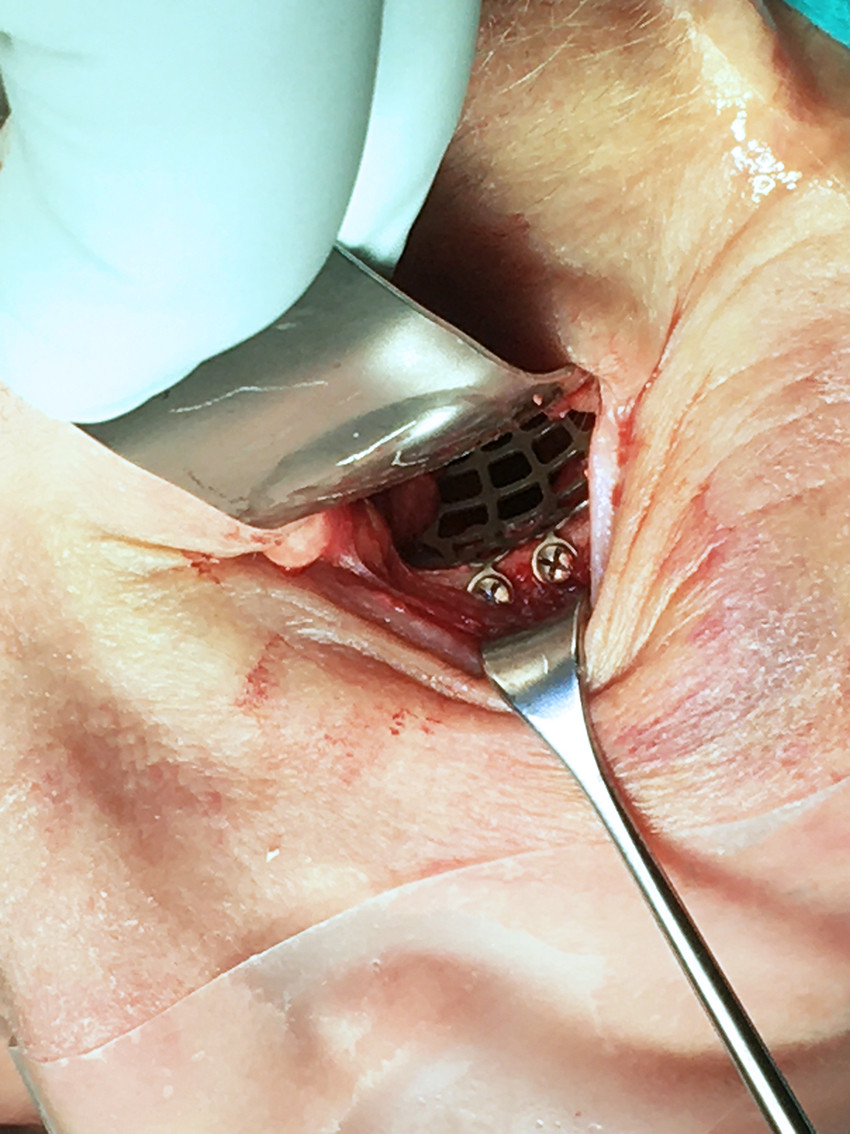

Tilgang til orbita oppnås enten transkutant eller transkonjunktivalt. Sistnevnte måte gir sjelden synlig arrdannelse og foretrekkes derfor ved frakturer i gulv og medialvegg. Figur 4 viser transkonjunktival tilgang med rekonstruksjonsplate i titan som er festet med skruer på nedre orbitakant. Ved større frakturer i medialveggen kan incisjonen forlenges transkarunkulært. Det samme gjelder lateralt, hvor man kan kombinere transkonjunktival tilgang med lateral kantotomi. Øvre blefaroplastikk-incisjon i hudfold på øvre øyelokk velges som regel ved frakturer i orbitataket. Ved kombinerte frakturer i orbitagulvet og nedre orbitakant velges ofte subciliær incisjon, som gir tilgang til reposisjon og osteosyntese av fraktur i nedre kant. Alternativt kan man legge incisjonen lenger nede, som ved subtarsal eller infraorbital tilgang. Sistnevnte brukes imidlertid kun hvis det allerede er kutt i huden, da denne tilgangen gir et dårligere kosmetisk resultat.